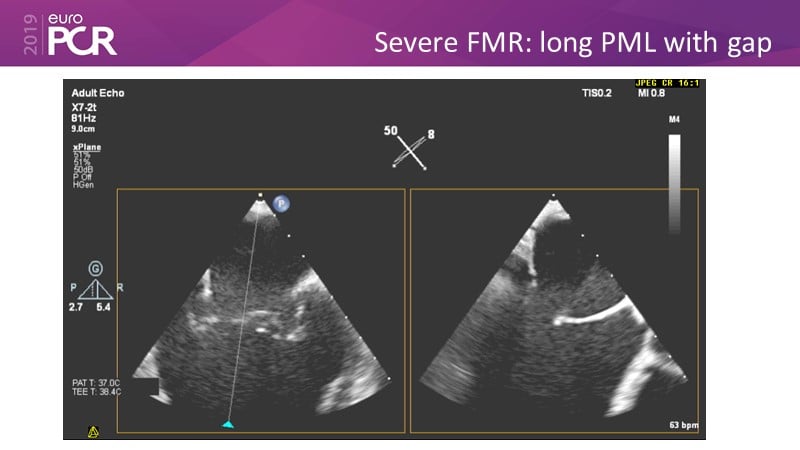

- To learn how will product innovation (Mitraclip NTR / XTR) drive improvement in procedural and clinical outcomes (EXPAND)